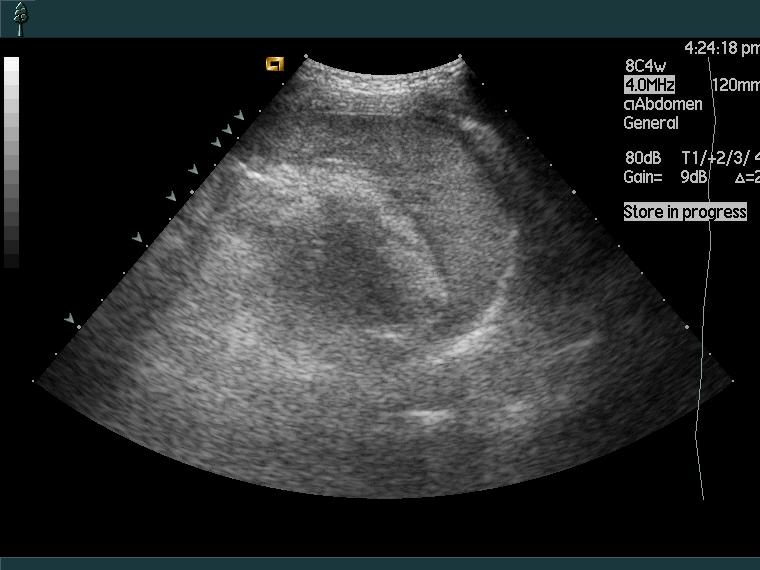

Обзорная рентгенография в случае внутреннего кровотечения помогает определить присутствие свободной жидкости (крови) в брюшной полости. При УЗИ органов малого таза и УЗИ брюшной полости выявляется источник кровотечения во внутренних органах и скопление анэхогенной жидкости. Основными методами диагностики кровотечения в брюшную полость являются эндоскопические исследования - лапароцентез (пункция брюшной полости с подключением шарящего катетера) и диагностическая лапароскопия.